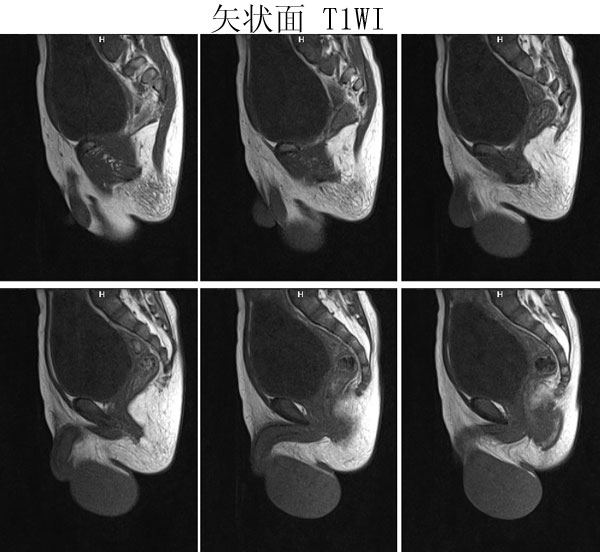

(广东同江医院的病例)男,2岁。左侧睾丸肿大3月,开始发现时红枣大,逐渐增大,现鸡蛋大小,表面光滑,无压痛,质地中等。

病理诊断 :(左侧)

睾丸胚胎性横纹肌肉瘤

,瘤组织局部浸润附睾组织,精索残端组织内未见瘤组织浸润。